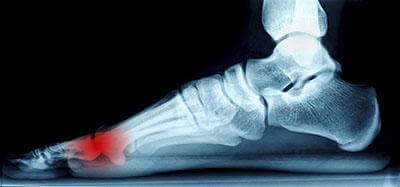

Neuroma (Morton's)

The pain caused by Morton’s neuroma is typically experienced at the ball of the foot. Many have described the sensation as feeling like they have a pebble stuck in their shoe. Because of this, those with the condition may find walking to be more difficult and uncomfortable. They may also experience a numbing or burning sensation in the foot. One of the most common factors that influence the development of Morton’s neuroma is improper footwear. Those who generally wear tightly fitted shoes or shoes with higher heels are more at risk at getting Morton’s neuroma. Having a foot abnormality may also increase the risk of getting this condition, as it may cause instability, thus adding more pressure onto the nerves of the foot. Certain foot conditions such as bunions, hammertoes, and flat flat feet have also been known to lead to Morton’s neuroma if not treated promptly.

Athletes have a tendency of getting Morton’s neuroma due to repetitive motions and pressure placed on the ball of the foot while running or jumping. Morton’s neuroma may also develop as a result of an injury to the foot.